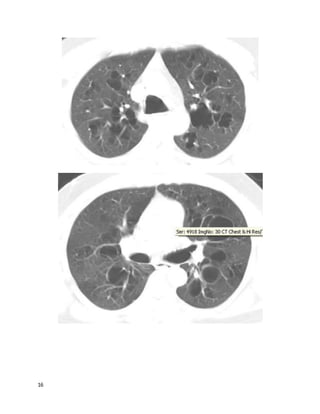

blood-streaked sputum. She lives in a high-rise retirement home. Other cuts of her

chest CT are similar to the one below, correlating well with the findings on chest

This is a mycobacterium avium complex infection, with Lady Windemere

syndrome (bronchiectasis and multiple small nodules often involving the right

middle lobe or lingula in nonsmoking elderly women, often with chest wall or

skeletal deformities). The other options are possible but the pattern on imaging

along with the history are most suggestive of MAC, an endemic organism inhaled

5

from soil or water. Her bronchiectasis could perpetuate her cough and hemoptysis;

however, she also has many nodules that are indicative of ongoing infection as the

primary process.Nontuberculous mycobacteria (NTM) also include M. kansasii,

rapidly growing mycobacteria (RGM), and numerous less common species.

Nonpathogenic airway colonization by these organisms is frequently incidentally

discovered and must be differentiated from infection. NTM infection commonly

causes a TB-like pattern (upper lobe cavitary disease); hypersensitivity

pneumonitis (ground glass and centrilobular nodules, sometimes with a mosaic

pattern), or the pattern seen here (nodular bronchiectasis with or without

fibrocavitary disease), along with low-grade nonspecific symptoms usually

including cough and fatigue.

Diagnosis requires compatible imaging and clinical findings, along with 2 positive

sputum samples (24+ hrs apart) or 1 positive sample from bronchoscopic lavage or

biopsy. This unfortunate woman has required more than 3 years of multi drug

therapy, with repeated medication switches for adverse effects including optic

neuropathy while on ethambutol--still, her sputum remains positive for MAC.

Unfortunately, her situation is not atypical for people with this indolent, difficult-

to-treat infection. National Jewish in Denver are the premier referral / consultation

center for these cases.